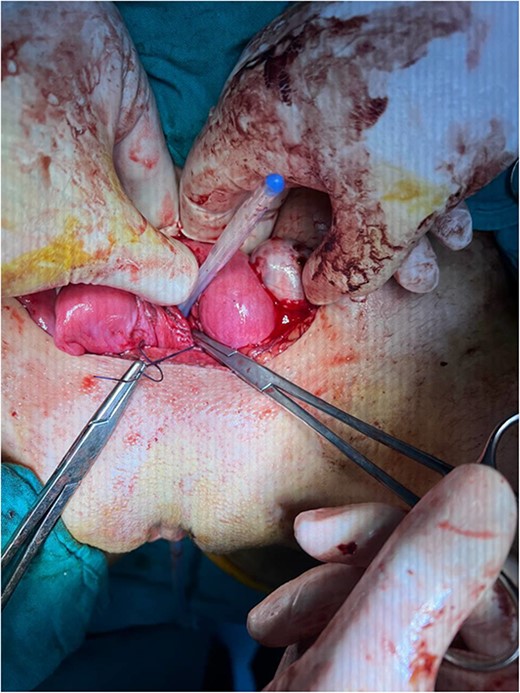

The hematomas were drained (Fig. 4), and upon investigation, two cervixes were found: one for each uterus and a single vagina with a closed end, representing a transverse vaginal diaphragm.

The didelphys uterus after the left fallopian tube and vaginal hematomas were drained.